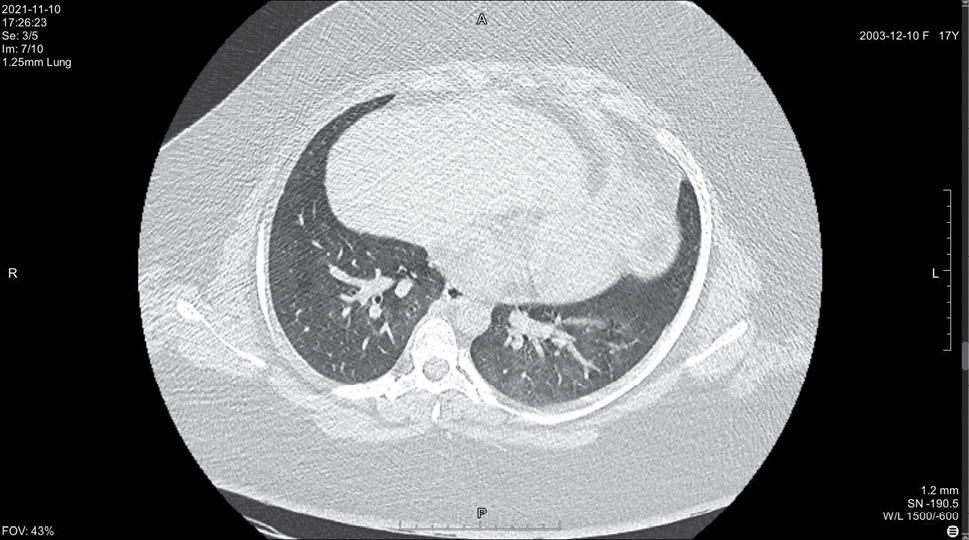

На 14 день болезни (10.11, 7 день госпитализации) была выполнена спиральная компьютерная томография грудной клетки, где выявлены признаки двусторонней интерстициальной полисегментарной пневмонии (рис. 1–8). Форма грудной клетки описана как обычная. Легочные поля расправлены. На томограммах бронхиальное дерево визуализировано до субсегментов: сами бронхи не деформированы, их просвет в пределах нормы, устья свободны, проходимость сохранена на всем протяжении. Во всех сегментах с обоих сторон определялись полиморфные, сливные участки уплотнения легочной ткани по типу матового стекла с участками консолидации. На этом фоне были видны просветы бронхов. Определялись фиброзные тяжи в проекции апикальной плевры обоих легких. Контуры диафрагмы четкие, синусы свободные, свободная жидкость в плевральной полости отсутствовала. Трахея обычной формы и размеров, карина острая. Сосудистые структуры верхнего средостения с четкими контурами и нормального диаметра, стенки сосудов без кальцинатов. Медиастинальные лимфоузлы и лимфоузлы корней обоих легких (без контрастного усиления) визуализированы единично, не увеличены. Сердце расположено обычно, размеры в пределах нормы. Выявлены умеренные дегенеративно-дистрофические изменения грудного отдела позвоночника. Мягкие ткани грудной клетки без особенностей. По заключению врача-рентгенолога, объем пораженной легочной паренхимы достигал 95%. Наиболее вероятно, что патологический процесс у пациентки имел вирусную природу.

Рисунок 5. Томограмма легких на уровне ThVII

Рисунок 6. Томограмма легких на уровне ThVIII